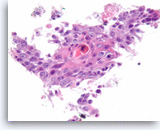

Ductal adenocarcinoma #1,

Pancreas FNA, Direct Smear.

The tumor cells have prominent intracytoplasmic vacuoles, irregular nuclear contours, vesicular chromatin and are arranged in three-dimensional clusters.

40X

Ductal adenocarcinoma #1,

Pancreas FNA, Direct Smear.

The tumor cells have prominent intracytoplasmic vacuoles, irregular nuclear contours, vesicular chromatin and are arranged in three-dimensional clusters.

40X